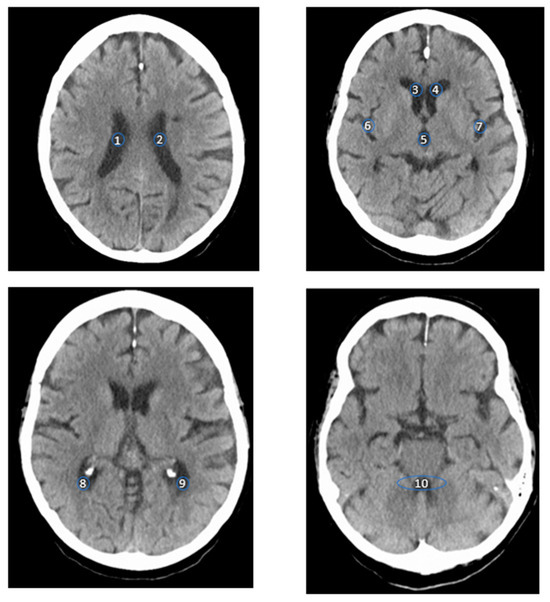

| a. Monoenergetic +67 keV HU—Measurements (HU) | ||||

|---|---|---|---|---|

| 5th Percentile | 10th Percentile | 90th Percentile | 95th Percentile | |

| Right LV AH | 5 | 6 | 14 | 15 |

| Right LV CP | 5 | 6 | 12 | 13 |

| Right LV PH | 6 | 7 | 14 | 16 |

| Left LV AH | 6 | 6.5 | 13 | 15 |

| Left LV CP | 5 | 6 | 12 | 13 |

| Left LV PC | 6 | 7 | 14 | 15 |

| 3rd V | 5 | 6 | 14 | 15 |

| 4th V | 6 | 6 | 13,5 | 15 |

| SF R | 8 | 9 | 17 | 19 |

| SF L | 5 | 8 | 18 | 19 |

| b. Virtual Native Phase (HU) | ||||

| Right LV AH | 3 | 5 | 13.5 | 15 |

| Right LV CP | 2 | 3 | 13 | 14 |

| Right LV PH | 2 | 4 | 15.5 | 18 |

| Left LV AH | 4 | 5 | 14 | 17 |

| Left LV CP | 2 | 3.5 | 12 | 14 |

| Left LV PC | 0 | 3 | 13 | 14 |

| 3rd V | 2 | 3 | 14.5 | 16 |

| 4th V | 3 | 4 | 12 | 14 |

| SF R | 4 | 6 | 18.5 | 21 |

| SF L | 5 | 6 | 18 | 19 |

| c. Iodine Phase (HU) | ||||

| Right LV AH | −5 | −4 | 5 | 7 |

| Right LV CP | −5 | −3 | 6 | 7 |

| Right LV PH | −6 | −4 | 6,5 | 7 |

| Left LV AH | −5 | −4 | 6 | 7 |

| Left LV CP | −4 | −3 | 5 | 6 |

| Left LV PC | −4 | −2 | 7 | 9 |

| 3rd V | −5 | −3 | 6 | 7 |

| 4th V | −3 | −2 | 7 | 7 |

| SF R | −5 | −4.5 | 7 | 10 |

| SF L | −5 | −3 | 7 | 8 |

| d. SNR | ||||

| SNR | ||||

| Right LV AH | 2.39 | |||

| Right LV CP | 2.29 | |||

| Right LV PH | 2.58 | |||

| Left LV AH | 8.17 | |||

| Left LV CP | 2.20 | |||

| Left LV PC | 2.65 | |||

| 3rd V | 2.33 | |||

| 4th V | 2.36 | |||

| SF R | 3.34 | |||

| SF L | 3.20 | |||